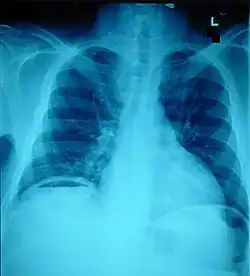

Ten percent of people with polytrauma who had no signs of abdominal injury did have evidence of such injuries using radiological imaging.[1] Diagnostic techniques used include CT scanning, ultrasound,[1] and X-ray.[7] X-ray can help determine the path of a penetrating object and locate any foreign matter left in the wound, but may not be helpful in blunt trauma.[7] Diagnostic laparoscopy or exploratory laparotomy may also be performed if other diagnostic methods do not yield conclusive results.[5]

The small intestine takes up a large part of the abdomen and is likely to be damaged in penetrating injury.[5] The bowel may be perforated.[4] Gas within the abdominal cavity seen on CT is understood to be a diagnostic sign of bowel perforation; however intra-abdominal air can also be caused by pneumothorax (air in the pleural cavity outside the lungs that has escaped from the respiratory system) or pneumomediastinum (air in the mediastinum, the center of the chest cavity).[4] The injury may not be detected on CT.[4] Bowel injury may be associated with complications such as infection, abscess, bowel obstruction, and the formation of a fistula.[4] Bowel perforation requires surgery.[4]